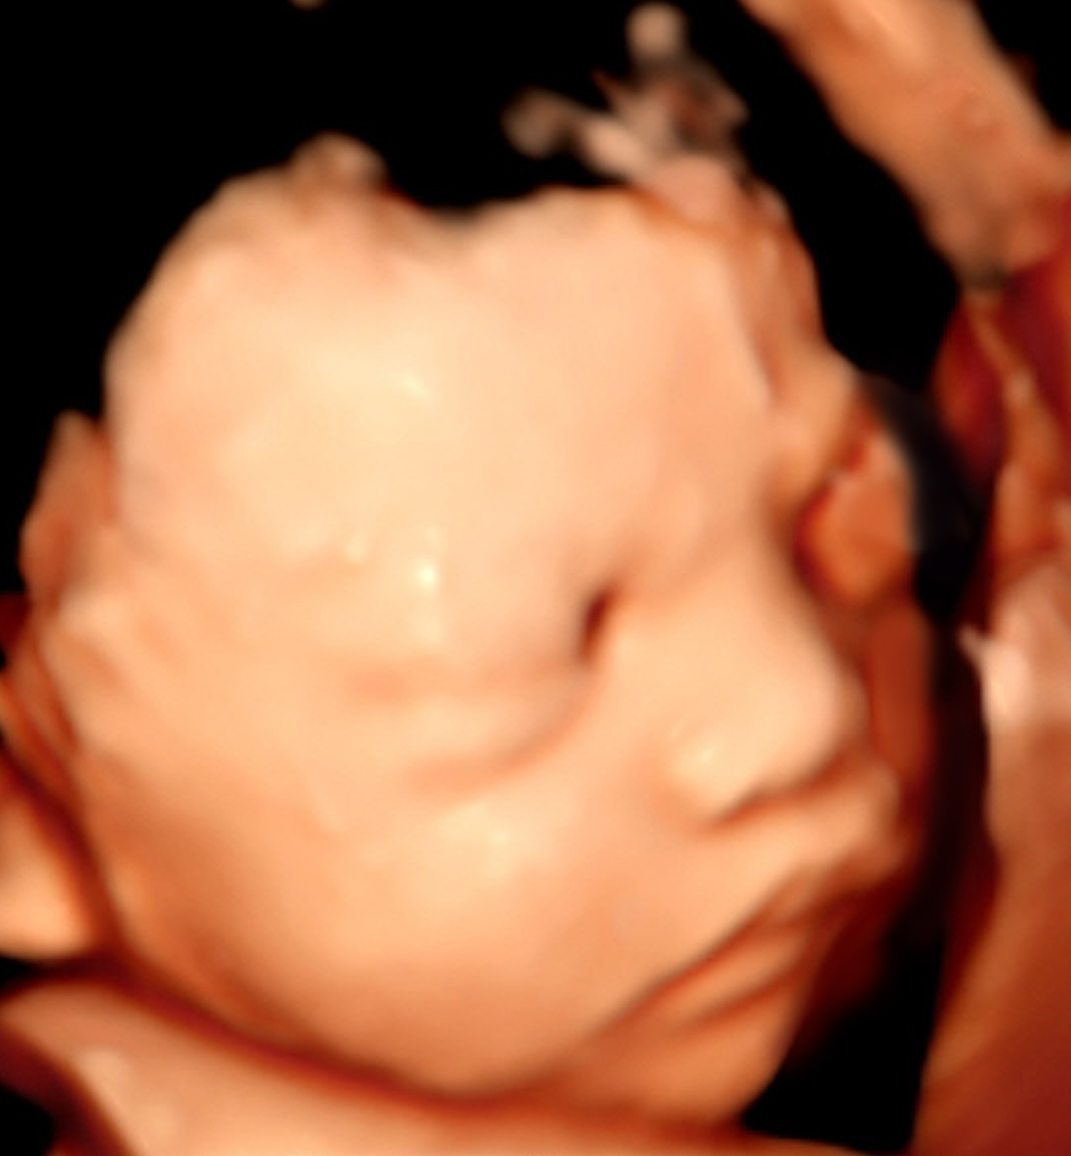

5D智能彩超拥有更高的分辨率和更强的图像处理能力,能够呈现出接近“IMAX电影画质”的细腻影像 。它采用一种被称为“水晶成像”的技术,能够穿透组织,将胎儿的骨骼、器官和组织结构以极其清晰、立体的形态展示出来。这种高清晰度对于观察胎儿微小的解剖结构细节至关重要,例如手指、脚趾、耳廓形态等,有助于医生发现一些在传统超声下不易察觉的细微异常,为排畸诊断提供了更丰富的视觉信息。

4. 温情互动,一次充满感动的“亲子会面”

除了严谨的医学诊断价值,5D彩超也为准爸妈们带来了无与伦比的情感体验。通过高清逼真的动态影像,您可以清晰地看到宝宝的每一个细微表情和动作,仿佛他(她)就在眼前。这份提前到来的“亲密接触”,不仅能极大地缓解孕期的焦虑,更能加深家庭成员与未出世宝宝之间的情感连接,让等待的每一天都充满更具体的幸福感。